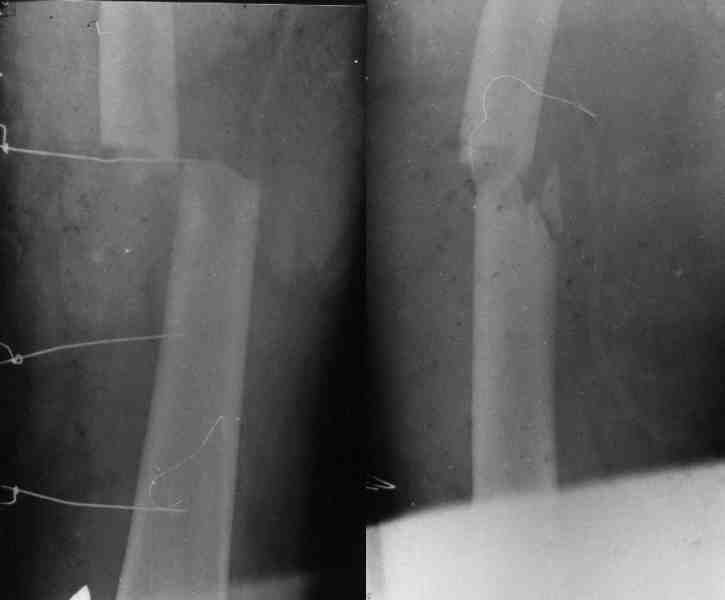

При рассверливании дистального отдела плеча будьте

осторожны, чтобы не получилось, как у моего партнера, во время установки интрамедуллярного

штифта римером раскололи вдребезги дистальный суженный бесканальный отдел плеча, после фиксация уже в двух сегментах, вот уже несколько лет не может смотреть на интрамедуллярный штифт для плеча.

Уважаемый Михаил Викторович! У нас имеется небольшой опыт блокируемых остеосинтезов плечевой кости (20-30), однако был печальный случай (у пациента, в другой клинике, плечо было оперировано гвоздем Кюнчера!!! - произошло отвисание дист фрагмента) , Нами был ваполнен БИОС (проксимальное блокирование одним винтом), через месяц произошло прорезывание порозной кости и погружение винта под кортикал с образованием диастаза между фрагментами, пришлось найти и извлечь этот винт, немного выбить стержень (не

вскрывая место перелома и не убитрая дистальные блокирующие винты) и выполнить проксимальное блокирование двумя винтами.